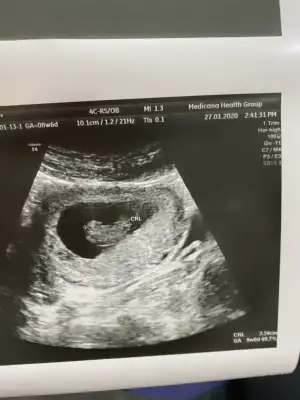

Dr + tam nuba denk getirmiş başka usg varmı12+4 banada yorumlarmisijizIkra meyra

Baska yokDr + tam nuba denk getirmiş başka usg varmı![]()

Bu göre kız ama tutmayabilir tekrar usg olursa paylaşın .usteki 12+3 usg de kafa yapısı kız gibi ama nub göremiyorum .13+ usg olursa paylaşırsınızBaska yok![]()

Bu göre kız ama tutmayabilir tekrar usg olursa paylaşın .usteki 12+3 usg de kafa yapısı kız gibi ama nub göremiyorum .13+ usg olursa paylaşırsınız![]()